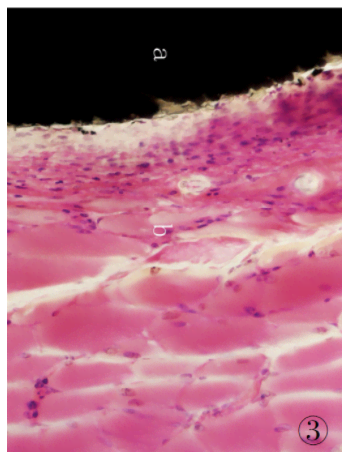

1.3.9 組織切片的染色將組織切磨片經(jīng)蒸餾水充分清洗后,參照文獻[5]的方法進行染色:蘇木精染液30 min,自來水充分沖洗,1%鹽酸乙醇分化30s,流水沖洗后再入溫水返藍,置伊紅染液5min,自來水沖洗,待組織切片自然干燥后經(jīng)Technovit 7210VLC封片,光鏡下觀察。制得的組織切片經(jīng)HE 染色后,細胞核、細胞質(zhì)著色對比鮮明,組織細胞形態(tài)清晰,可直接在光學(xué)顯微鏡下進行組織學(xué)觀察,可見植入的CF/PEEK 復(fù)合材料與周邊肌肉組織結(jié)合緊密( 圖2、3) ,植入的復(fù)合材料周圍可見新生纖維結(jié)締組織,纖維囊壁結(jié)構(gòu)已形成。

圖3 高倍鏡下埋置有CF/PEEK 復(fù)合材料的肌肉組織病理切片:a.試驗樣品CF/PEEK復(fù)合材料; b.肌肉組織